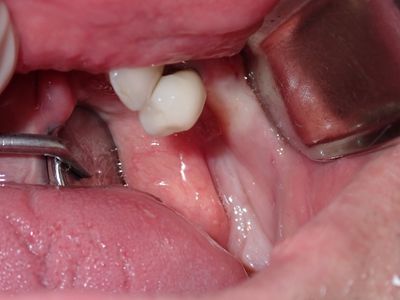

Bone loss noted, bone graft required, upon flapping, decided to place implants. Difficult case due to very strong macroglossic tongue, limited sulcular space. Short and wide implants placed, all socket/defects grafted with sticky bone from cortical allograft. membrane placed interimplant and fibrin membrane also used